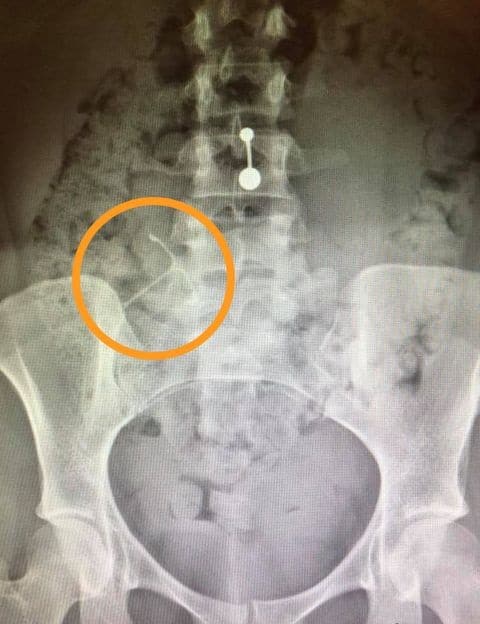

Μια άλλη γυναίκα, η Β.Τ., ανέφερε ότι ο γιατρός της απέρριψε τα παράπονά της για έντονο πόνο, για να συνειδητοποιήσει εβδομάδες αργότερα ότι το σπιράλ είχε τρυπήσει τη μήτρα της και είχε σφηνώσει σε μια παρακείμενη μάζα λίπους. Αυτό δυστυχώς δεν είναι το μόνο περιστατικό μετακίνησης του σπιράλ εκτός της μήτρας και τρώσης γειτονικών οργάνων που προκαλεί ανάλογα σοβαρά προβλήματα.